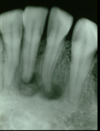

what other radiographs other than periapicals can be used to assess periapical inflamm pathology?

A